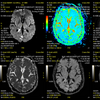

IRM Cérébrale

L’IRM cérébrale est un examen qui permet de détecter des anomalies cérébrales et d’en déterminer les causes (dégénérative, infectieuse, vasculaire, tumorale ou  inflammatoire)